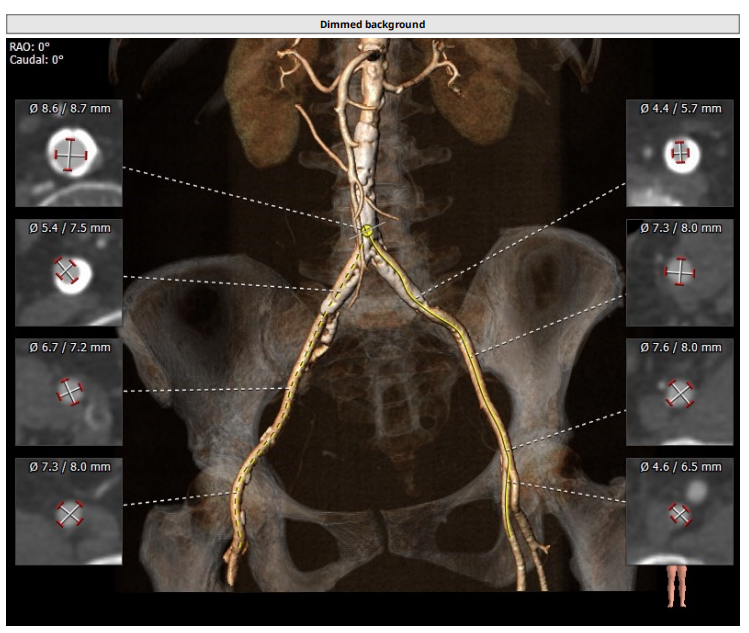

术前CT评估报告

1、入路条件差,髂动脉血管钙化十分严重,通路建立难度极大。

2、主动脉瓣置换术后,瓣口面积极小,导致瓣膜无法稳定锚定,需要术中时刻观察调整。

3、升主动脉最宽处约44.5mm,心脏角度大,约50°,备Snare辅助。